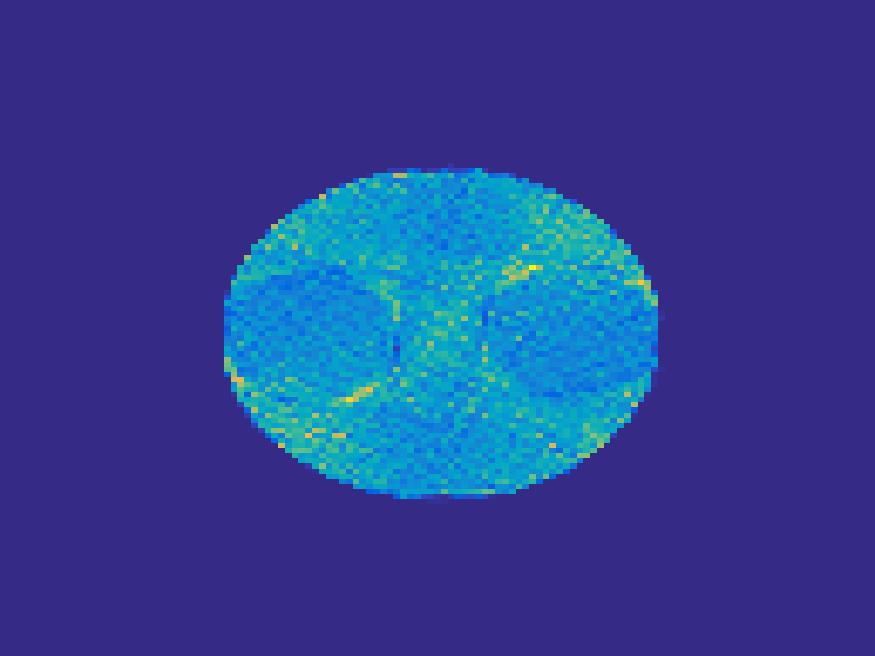

For the simulated images of rat’s abdomen, the same procedure is applied to generate projection data. Also, noise was added to the sinogram. Figure 5 compares the frames reconstructed by different methods. Clearly, the traditional FBP method and least square method cannot reconstruct the dynamic images with very few projections, however the proposed method reconstructs the images quite accurately. Figure 6 illustrates the comparison of the true TACs and those reconstructed by the proposed method. We can see that they are quite accurate and present small errors.

| Frame 1 | Frame 11 | Frame 21 | Frame 31 | Frame 41 | Frame 51 | Frame 61 | Frame 71 | Frame 81 |